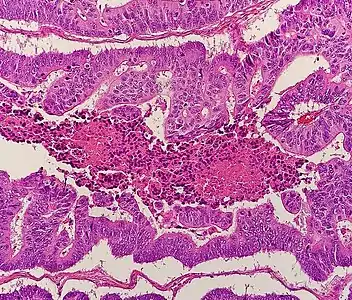

Micrograph of colorectal adenocarcinoma, showing "dirty necrosis".

The histopathologic characteristics of the tumor are reported from the analysis of tissue taken from a biopsy or surgery. A pathology report contains a description of the microscopical characteristics of the tumor tissue, including both tumor cells and how the tumor invades into healthy tissues and finally if the tumor appears to be completely removed. The most common form of colon cancer is adenocarcinoma, constituting between 95%[85] and 98%[86] of all cases of colorectal cancer. Other, rarer types include lymphoma, adenosquamous and squamous cell carcinoma. Some subtypes are more aggressive.[87] Immunohistochemistry may be used in uncertain cases.[88]